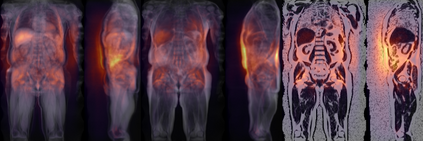

Along with rich health-related metadata, an ongoing imaging study has acquired MRI of over 40,000 male and female UK Biobank participants aged 44-82 since 2014. Phenotypes derived from these images, such as measurements of body composition, can reveal new links between genetics, cardiovascular disease, and metabolic conditions. In this retrospective study, six measurements of body composition were automatically estimated by ResNet50 neural networks for image-based regression from neck-to-knee body MRI. Despite the potential for high speed and accuracy, these networks produce no output segmentations that could indicate the reliability of individual measurements. The presented experiments therefore examine mean-variance regression and ensembling for predictive uncertainty estimation, which can quantify individual measurement errors and thereby help to identify potential outliers, anomalies, and other failure cases automatically. In 10-fold cross-validation on data of about 8,500 subjects, mean-variance regression and ensembling showed complementary benefits, reducing the mean absolute error across all predictions by 12%. Both improved the calibration of uncertainties and their ability to identify high prediction errors. With intra-class correlation coefficients (ICC) above 0.97, all targets except the liver fat content yielded relative measurement errors below 5%. Testing on another 1,000 subjects showed consistent performance, and the method was finally deployed for inference to 30,000 subjects with missing reference values. The results indicate that deep regression ensembles could ultimately provide automated, uncertainty-aware measurements of body composition for more than 120,000 UK Biobank neck-to-knee body MRI that are to be acquired within the coming years.